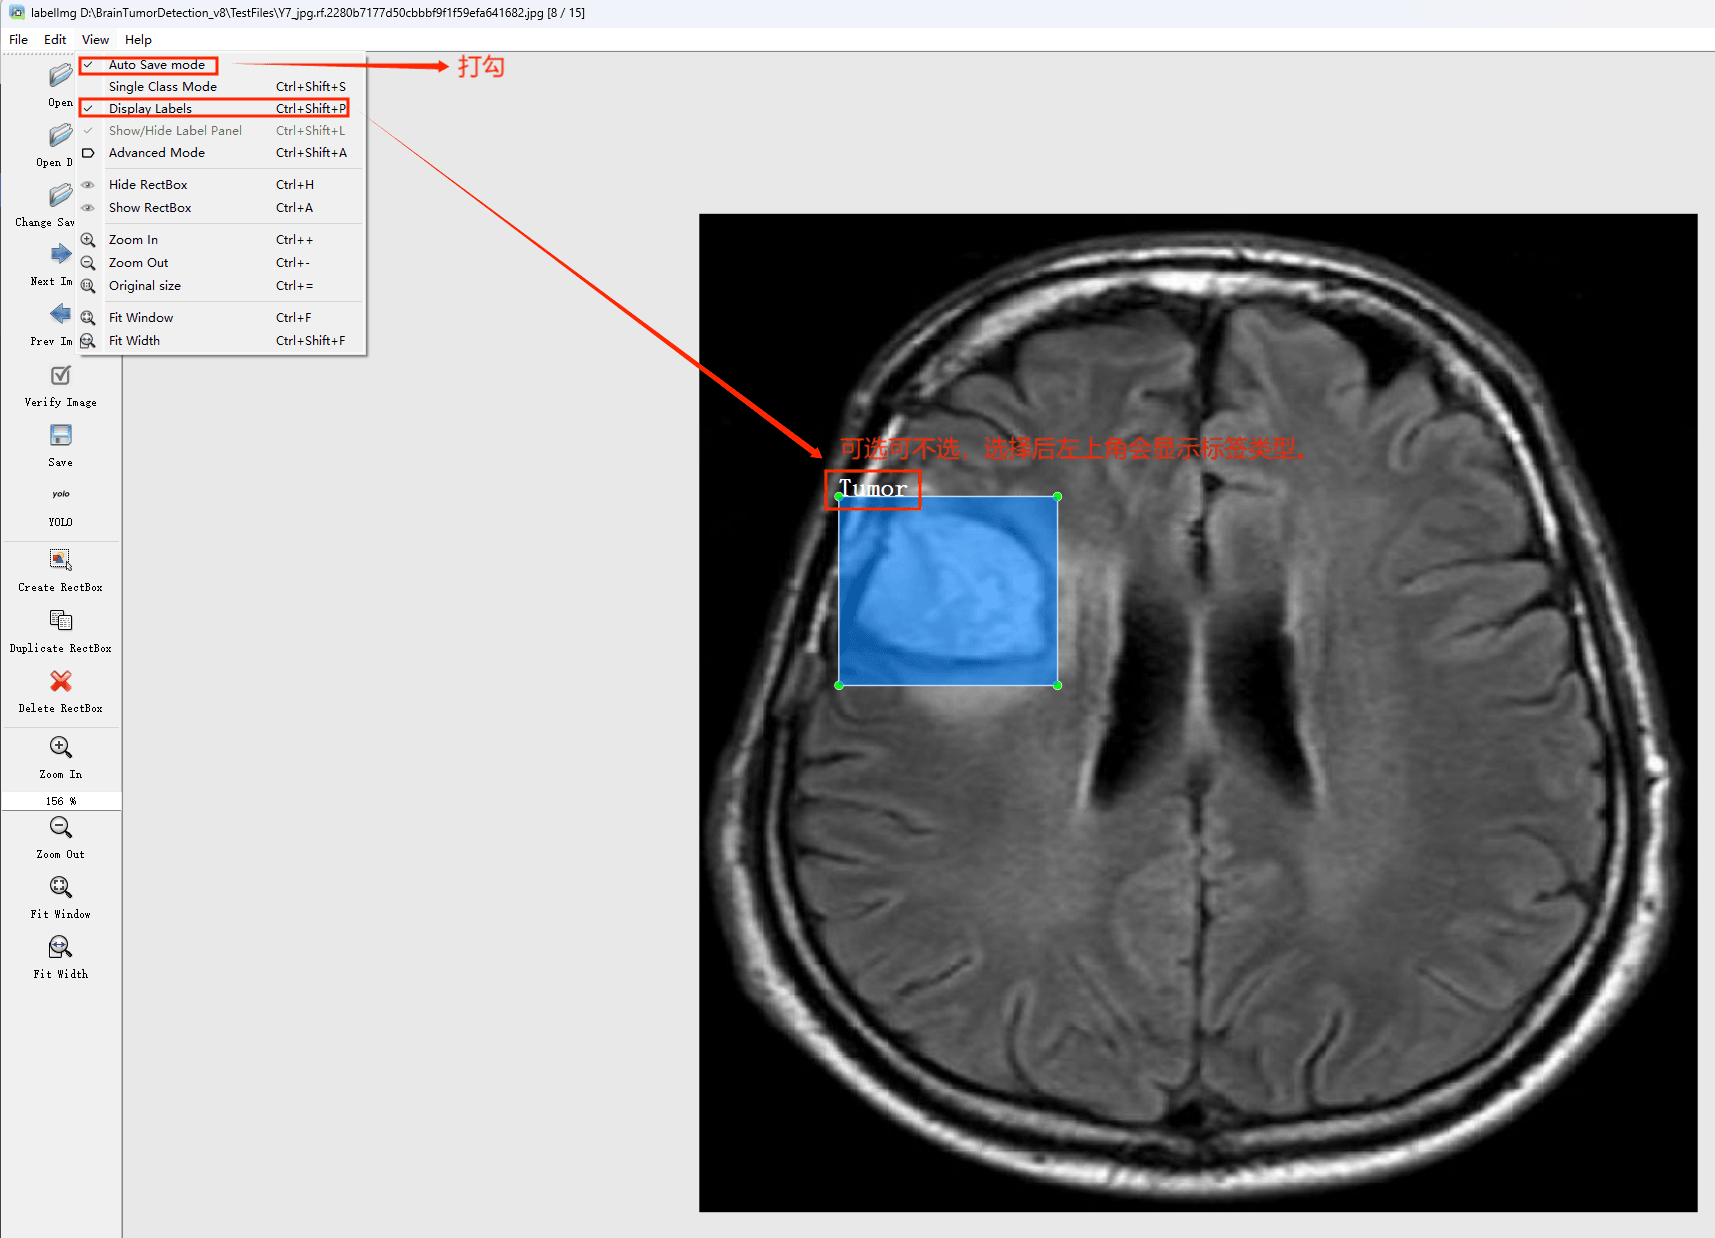

在View中勾选Auto Save mode

接下来我们打开需要标注的图片文件夹

并设置标注文件保存的目录(上图中的Change Save Dir)

接下来就开始标注,画框,标记目标的label,然后d切换到下一张继续标注,不断重复重复。